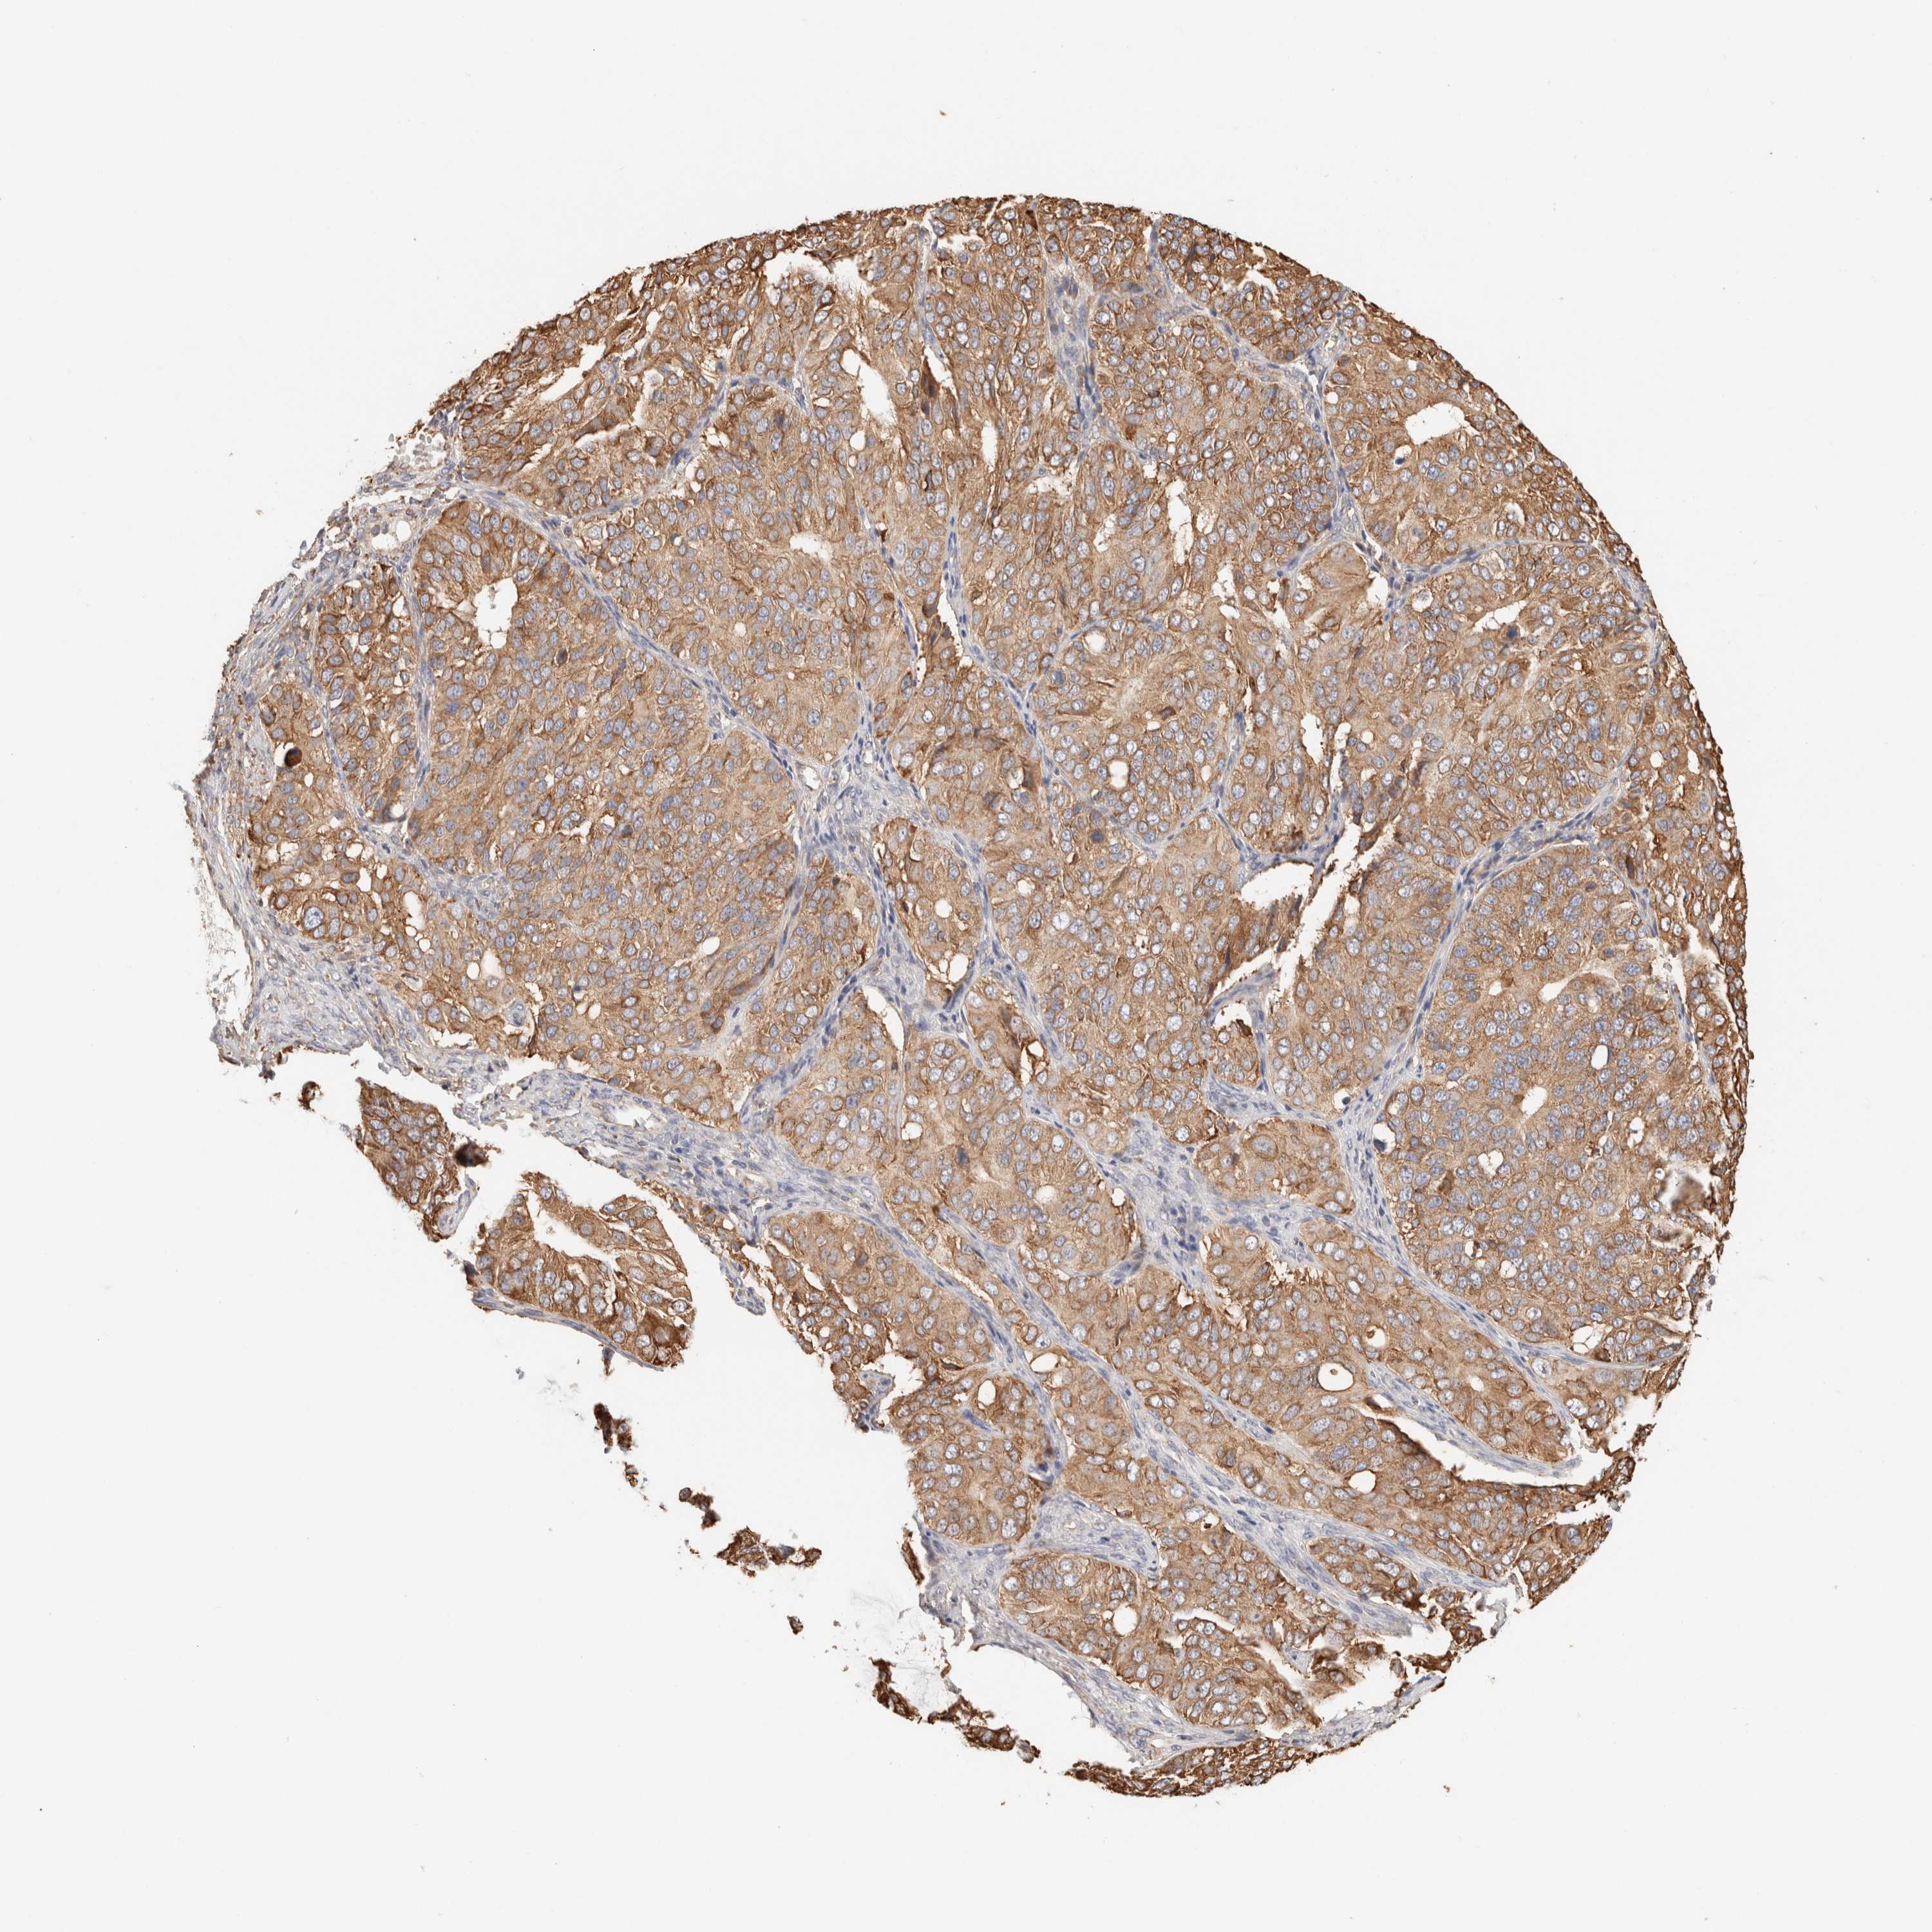

OVARIAN CANCER - Protein expressioni

A mouse-over function shows sample information and annotation data. Click on an image to view it in a full screen mode. Samples can be filtered based on level of antibody staining by selecting one or several of the following categories: high, medium, low and not detected. The assay and annotation is described here.

Note that samples used for immunohistochemistry by the Human Protein Atlas do not correspond to samples in the TCGA dataset.

Antibody stainingi

Antibody staining in the annotated cell types in the current human tissue is reported as not detected, low, medium, or high, based on conventional immunohistochemistry profiling in selected tissues. This score is based on the combination of the staining intensity and fraction of stained cells.

Each image is clickable and will lead to virtual microscopy that enables deeper exploration of all samples and also displays staining intensity scores, fraction scores and subcellular localization as well as patient and tissue information for each sample.

Antibody HPA007641

Antibody CAB022464

Staining

High

Medium

Low

Not detected

Intensity

Strong

Moderate

Weak

Negative

Quantity

>75%

75%-25%

<25%

None

Location

Nuclear

Cytoplasmic/membranous

Cytoplasmic/membranous,nuclear

Cystadenocarcinoma, serous, NOS

Carcinoma, endometroid

Cystadenocarcinoma, mucinous, NOS

Carcinoma, NOS